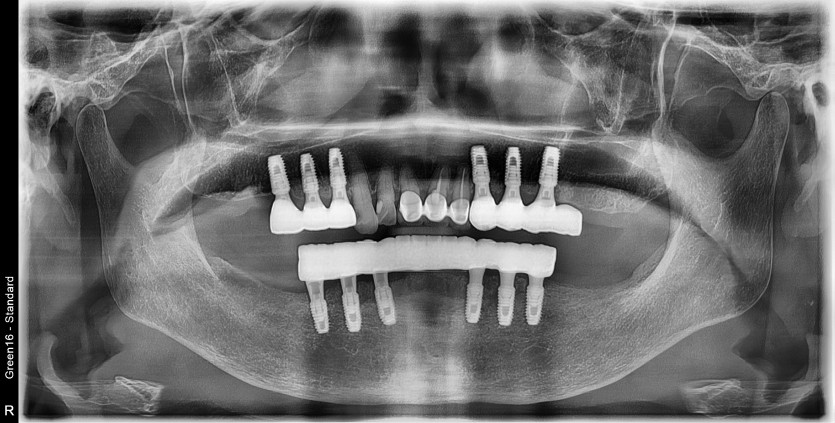

만 82세 하악 풀아치, 상악 임플란트(일부) 증례

하악 풀아치 증례입니다. (상악 구치부 임플란트 포함)

12개의 임플란트로 완성하였습니다.